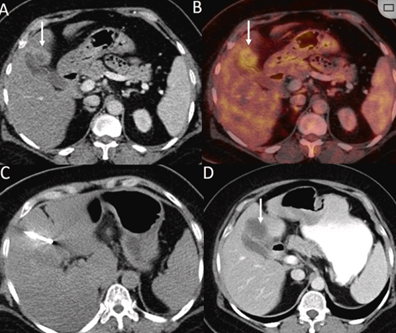

79 岁男性,肝转移(结直肠癌)肿瘤的完全消融病例

( a ) 轴向 MRI 和 ( b ) 轴向 CT 显示肝S8段有一个16mm的病灶,邻近肝缘。( c )冷冻消融期间CT显示放置了2个冷冻探针,低密度冰球包围病灶。(d)术后1个月随访 CT显示冰球对应的坏死区域,未见复发。(f)与基线影像(g)相比,12个月后的FDG-PET/CT显示未见FDG摄取。

(a)轴向CT显示病变位置毗邻心脏和上腔静脉(黑色箭头)。1个月后的轴向(e)和冠状位(f)增强CT扫描显示低密度区域,由于肉芽组织反应引起的边缘增强。

技术成功100%,92% 的病灶中观察到肿瘤完全消融。16 名患者 (33%) 出现局部复发。10 名患者 (20%) 因局部复发或肿瘤消融不完全而接受二次冷冻消融术。